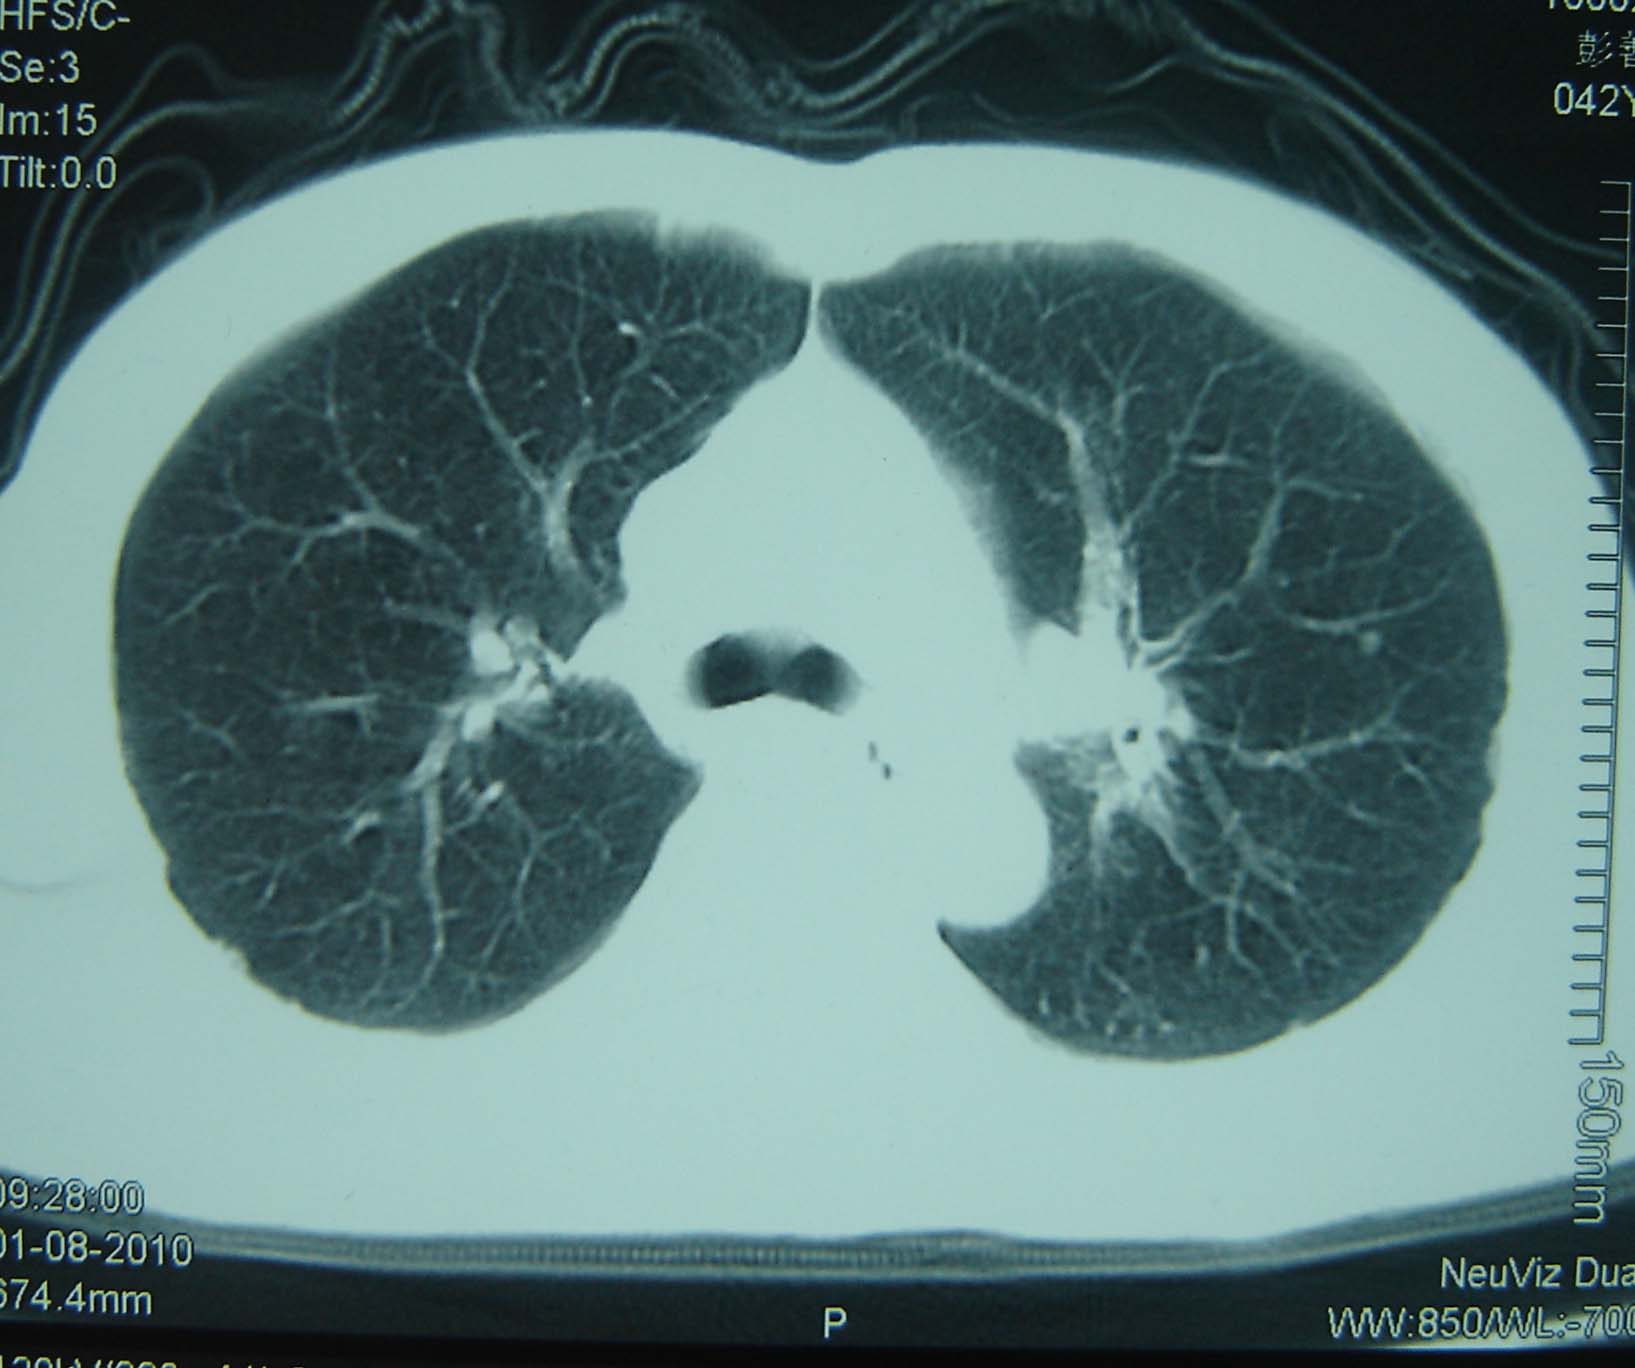

男 、43岁,咳嗽胸痛,装修工,平时接触粉尘较多,有吸烟史10多年,纤维支气管镜检查未发现异常,胃镜、腹部b超检查亦未发现异常,颈部淋巴结活检未发现肿瘤细胞。

不能排除转移,如果不能找到原发灶,只有短期随访。

结节病?转移瘤?

结节病。

转移瘤?

1)考虑双肺及胸膜多发性转移瘤。2)肺气肿。

双肺结节病。